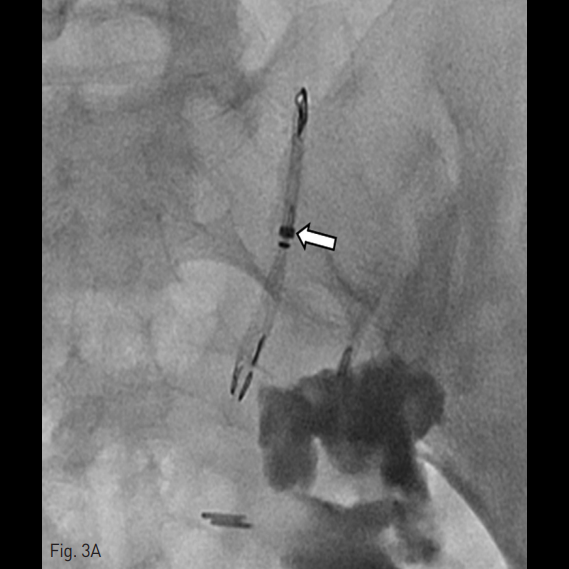

성공적으로 스텐트를 위치시킨 것이 확인된 후 (Fig. 3A) 조영제를 재주입하여 추가적인 누출이 없는 것을 확인하였다 (Fig. 3B).

18개월 후 시행한 순방향 요관조영술 상에서 조영제의 누출 및 스텐트의 이동이 없는 것을 확인하였다 (Fig. 3C).

Fig. 3. Percutaneous placement of the ureteral occlusion stent.

B. Ureterogram obtained immediately following stent deployment shows complete occlusion of the ureter without further contrast medium leakage.

C. An 18-month follow-up ureterogram shows neither contrast medium leakage nor occlusion stent migration (arrows).